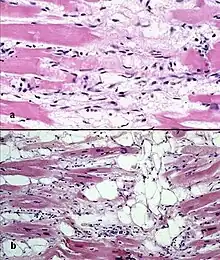

![]() | |

| Typical micro-histologic features of ARVC/D. Ongoing myocyte death (upper) with early fibrosis and adipocyte infiltration (lower). | |

There are two pathological patterns seen in ACM, Fatty infiltration and fibro-fatty infiltration.

Fatty infiltration

At first, fatty infiltration, is confined to the right ventricle. This involves a partial or near-complete substitution of myocardium with fatty tissue without wall thinning. It involves predominantly the apical and infundibular regions of the RV. The left ventricle and ventricular septum are usually spared. No inflammatory infiltrates are seen in fatty infiltration. There is evidence of myocyte (myocardial cell) degeneration and death seen in 50% of cases of fatty infiltration.

Fibro-fatty infiltration

The second, fibro-fatty infiltration, involves replacement of myocytes with fibrofatty tissue. A patchy myocarditis is involved in up to 2/3 of cases, with inflammatory infiltrates (mostly T cells) seen on microscopy. Myocardial atrophy is due to injury and apoptosis. This leads to thinning of the RV free wall (to < 3 mm thickness) Myocytes are replaced with fibrofatty tissue. The regions preferentially involved include the RV inflow tract, the RV outflow tract, and the RV apex. However, the LV free wall may be involved in some cases. Involvement of the ventricular septum is rare. The areas involved are prone to aneurysm formation.